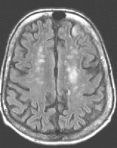

Fig. 1 Fig. 2 Fig. 3 Fig. 4

MRI Findings: In the supratentorial regions, some atrophy and chronic small vessel deep white matter ischemic changes were observed (Fig. 1) but no acute lesion or infarct was observed on MR diffusion. In the posterior fossa, however, a subtle small 1 cm hyperintensity can be seen in the left side of medulla on T2 weighted (Fig. 2) and FLAIR images (Fig. 3). This can be seen with an infarct, but its age would remain indeterminate. The MR diffusion image (Fig. 4) shows hyperintensity in the same region consistent with an acute infarct (arrows) as opposed to chronic ischemic changes.

Final Diagnosis: Based on the MR appearance, diagnosis of acute lateral medullary infarct was provided. This is a classic appearance of a posterior inferior cerebellar artery (PICA) infarct (PICA Syndrome), which may have thrombosed.

Conventional imaging may not be able to detect hyperacute strokes or differentiate acute from chronic infarcts. With MR diffusion, detection of acute infarcts is immediate and differentiation from old infarcts is obvious. This is due to its ability to allow discrimination between cytotoxic edema (present in acute infarcts) from vasogenic edema (seen with a variety of other brain lesions including neoplasms), sometimes not possible with conventional MR imaging. Only cytotoxic edema is hyperintense on diffusion-weighted images. Diffusion MR images show abnormal hyperintensity in acute infarcts from minutes to 7-14 days after stroke.*